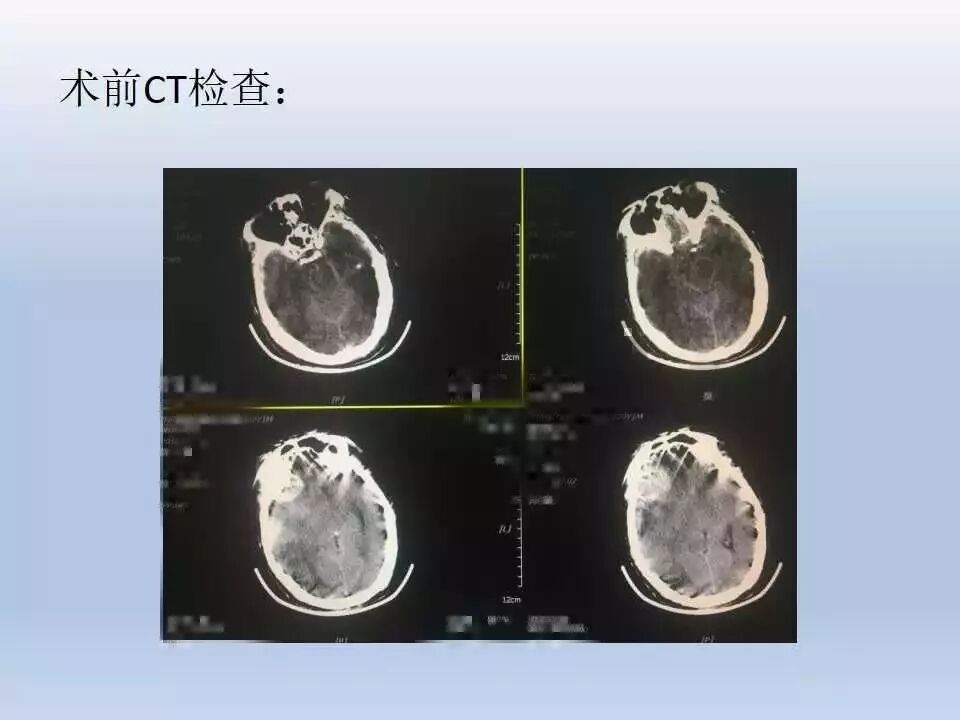

该患者伤后1小时入院,CT提示右额颞叶挫裂伤,GCS15分,伤后21小时嗜睡,复查CT显示右额颞挫裂伤血肿加重并硬膜下血肿,在谈话准备手术时突然呼吸心跳停止。从受伤时完全清醒到短时间内即进展至呼吸心跳停止,符合“talk and die”现象。入院时脑挫裂伤不重,GCS15分,没有ICP监测的指征。要防止“talk and die”现象的发生,需要严密观察,并要动态CT复查。该患者首次CT检查距离伤后约1小时左右,比较早,但损伤仍继续进展。有文献建议要在伤后6h、12h、24h动态复查,及时发现损伤进展,及早干预,避免发生“talk and die”现象。如果能够及早复查CT发现进展出血,及早干预或许会更好。